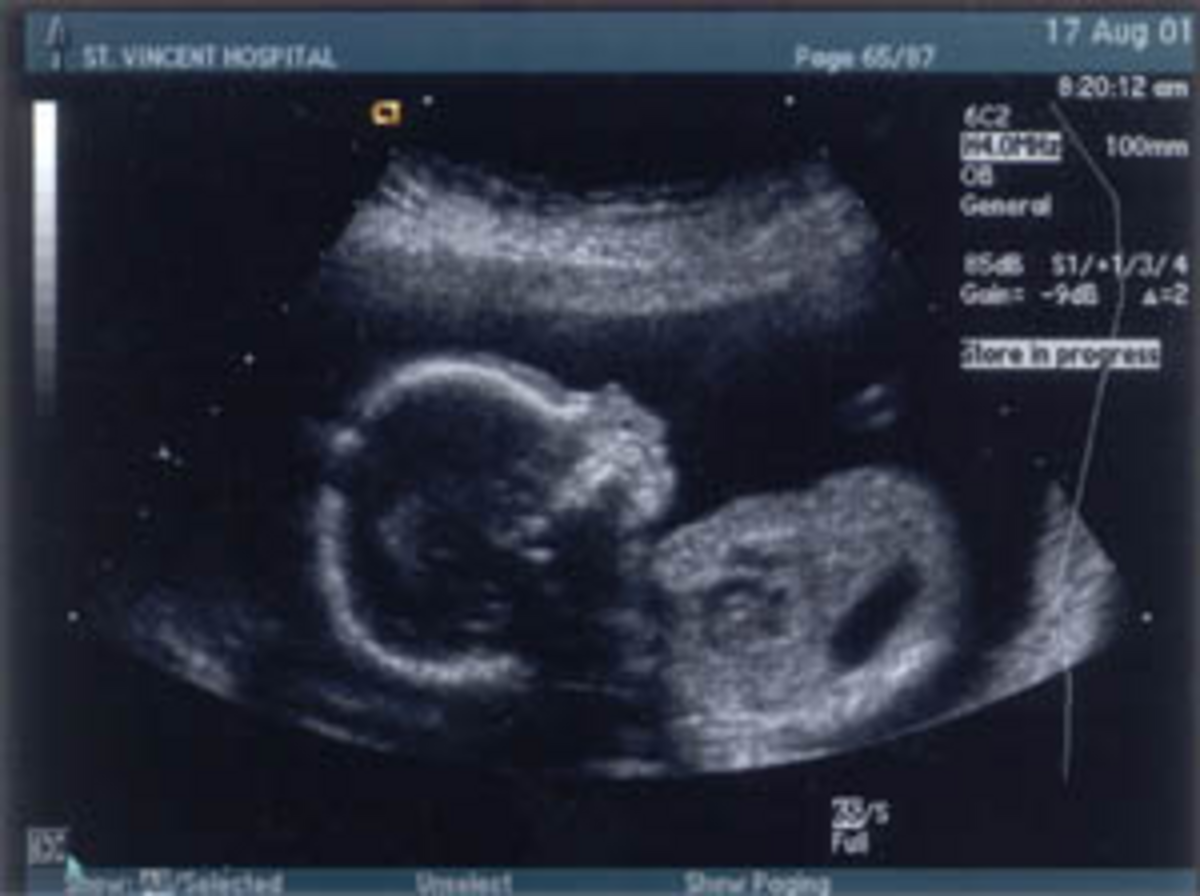

Jeffrey et moi avons annoncé à nos parents, familles, et amis, que nous attendions un enfant. C'était le premier petit enfant des deux côtés de la famille. Il allait être le premier neveu pour nos frères et sœurs. Son arrivée était grandement attendue. Mon docteur était inquiet à cause de mes problèmes de santé et nous avons eu une échographie précoce à la 8e semaine pour être sûrs que notre petit se développait correctement. Il nous a été dit que le bébé était petit pour sa gestation, mais que c'était peut-être dû à un mauvais calcul de la date du terme. J'ai été malade tous les jours de la grossesse déjà avant de savoir que j'étais enceinte et jusqu'à très tard dans la grossesse.

Le technicien a commencé l'échographie, commentant combien mon ventre était petit. Elle a mentionné qu'elle ne pouvait pas voir le bébé comme il faut et devait appeler le docteur. Le docteur est arrivé dans la pièce et, après seulement une minute, il a dit : « Il n'y a aucune bonne manière d'annoncer cela. Voulez-vous parler ici ou dans le bureau, car il y a quelque chose d'anormal avec votre bébé. » Jeffrey a commencé à pleurer et a serré ma main. Je voulais savoir immédiatement, pendant que je me tenais sur la table, avec mon bébé à l'écran.

Il dit : « Votre bébé a un défaut de naissance comme vous en avez parlé avec le conseiller. Le bébé a une anencéphalie. Il y a un taux de mortalité de 100% avec cette malformation. »

Nous avons demandé une échographie pour déterminer le sexe de notre bébé, car nous n'avions jamais pu en être sûr lors des précédents échographies. Nous avons découvert au 7e mois que nous allions avoir un garçon. Je sais que ça a fait d'autant plus mal à mon mari. Ce n'est pas qu'il n'aurait pas autant aimé une fille, mais je sais les rêves qu'il avait d'avoir un fils. Nous l'avons appelé Brandon, ce qui signifie phare. Il allait aller à la maison de notre Seigneur et être notre phare pour trouver notre chemin vers lui.